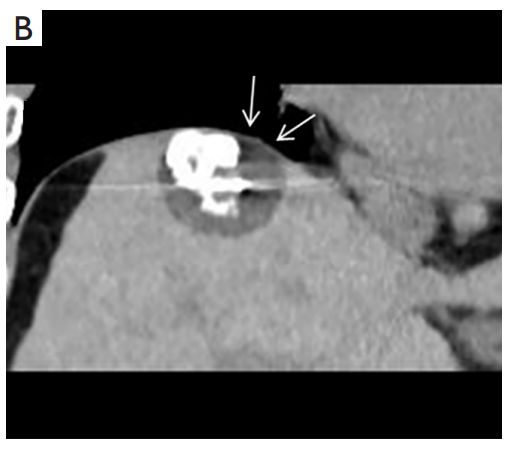

背景:由于一些原因,位于膈肌附近的腫瘤的熱消融在技術(shù)上具有挑戰(zhàn)性。首先,術(shù)中計算機掃描和超聲檢查無法清晰顯示射頻消融/微波消融切緣。第二,消融過程中不利的針分布和過熱可能導(dǎo)致肝包膜破裂,并對膈、肺和心臟造成嚴重損傷。第三,即使使用人工腹水,仍有9~22%的患者因肝周粘連或腫瘤位置靠近肝表面而導(dǎo)致膈肌熱損傷。冷凍消融可能是毗鄰膈肌的HCC的一種有前途的治療方法,因為在消融過程中使用CT和US可以很好地顯示腫瘤邊緣。盡管一些研究評估了在高危區(qū)域使用冷凍消融治療HCC,但很少有研究針對膈肌臨近區(qū)域。

背景:肝癌是中國最常見的惡性腫瘤之一,發(fā)病率和死亡率都很高。雖然手術(shù)切除是最好的治療方法,但大多數(shù)患者處于晚期或直到住院才有手術(shù)指征。對于單個腫瘤直徑小于5厘米的患者,微創(chuàng)治療與手術(shù)切除效果相當;多個病灶小于3個,單個病灶最大直徑小于3cm;不侵犯血管、膽管、鄰近器官和遠處轉(zhuǎn)移。雖然一些傳統(tǒng)消融技術(shù)方式可以使部分患者受益,但不適用于特殊部位肝癌(定義為毗鄰大血管、肝外臟器和重要結(jié)構(gòu)的腫瘤)的治療。冷凍消融作為一種相對較新的治療方式,具有明顯的冰球效果、療效好、激活抗腫瘤免疫、并發(fā)癥發(fā)生率低等優(yōu)點,尤其適用于特殊部位肝癌患者的治療。我們的研究目的是探討CA治療特殊部位肝癌的安全性、可行性和有效性。